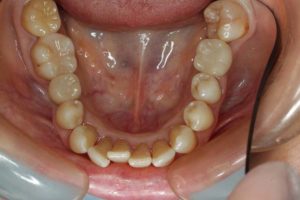

どのように変わったか、下の写真をご覧ください。

長い間お疲れ様でした。この患者さんは、奥歯を何本も失っていて満足なお食事ができない状態でした。前歯も所々虫歯で黒ずんでいて気になって口を開けて笑えないとおっしゃっていました。そもそも、最初はお嬢様の結婚の前までに綺麗にしたいというものだったのですが、治療をしていくうちに奥歯の大切さを実感していただいたようです。

奥歯にインプラントを入れ、前歯はホワイトニングやダイレクトボンディング、セラミックなどで修復しました。